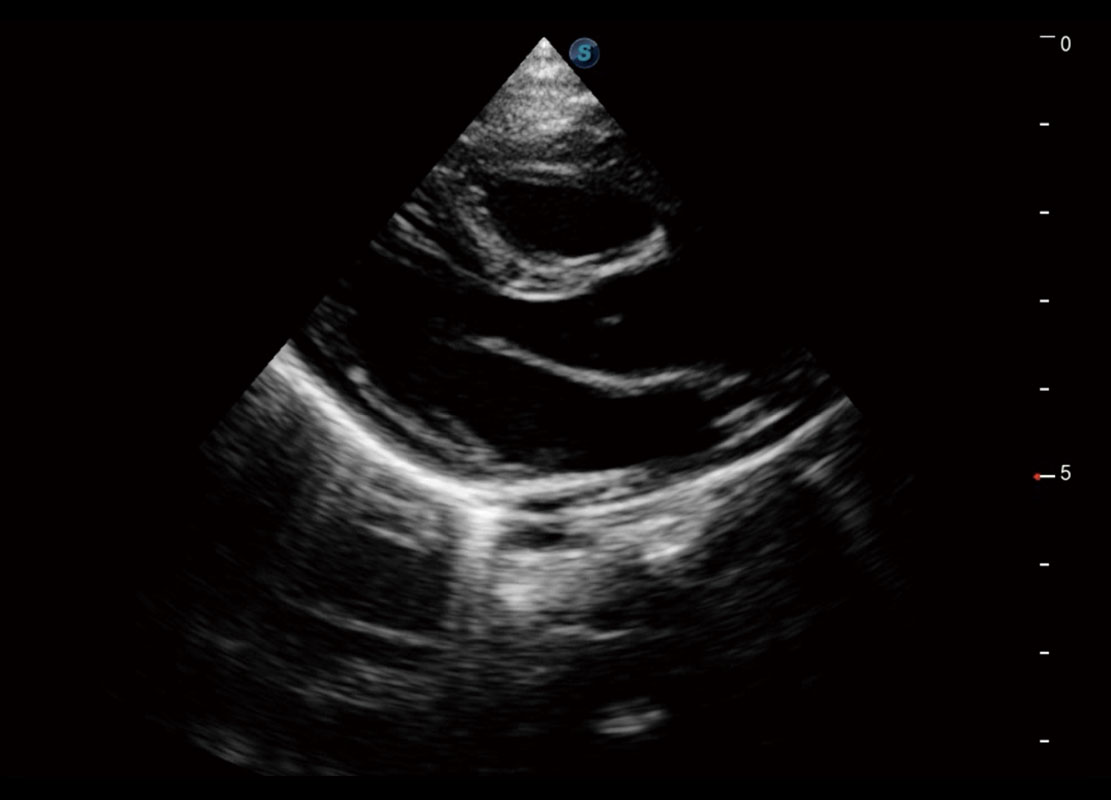

四腔切面

P60搭载一系列胎儿心脏成像技术,实现精细的胎儿心脏评估。